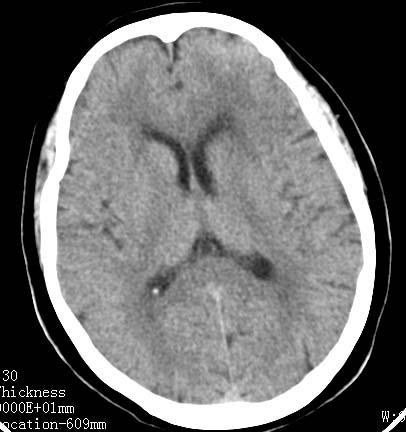

标题: CT17832:女性病人 65岁语言障碍一天 [打印本页]

女性病人 65岁语言障碍一天

左脑额顶等底密度肿块,灶周水肿明显,占位效应(+),考虑为转移瘤.(不考虑是胶质瘤.)

病灶中心为等密度,周边绕以低密度水肿区,考虑左额叶占位性病变。